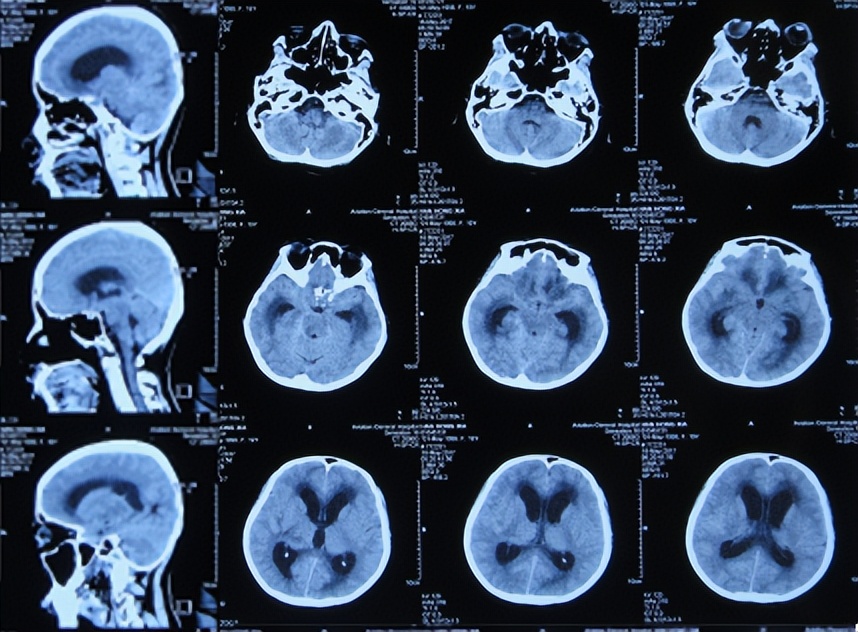

但发病后5天即2017年3月25日,从学校宿舍的上铺下来时因发热虚弱摔下,右眼眶外伤,就诊于第1家的陕西省西安某三甲医院,查脑CT( 图-1 )后认为右额颞部硬膜下有血肿,胸部X线检查未见异常(片子丢失)。

图-1: 2017年3月25日脑CT